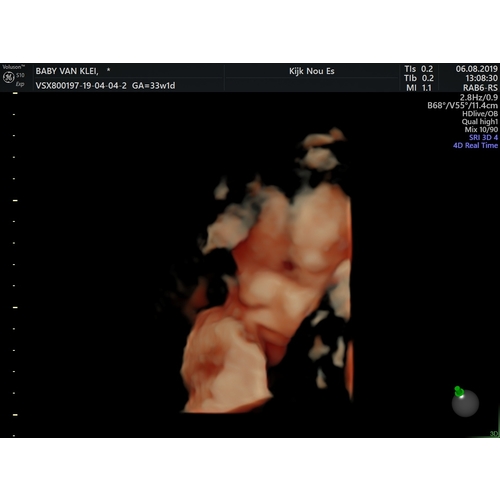

Ik ben net geweest met 33 +1 ze was haast nergens te zien ookal is ze aardig eigewijs al馃槀dit was de enige duidelijke..馃槕